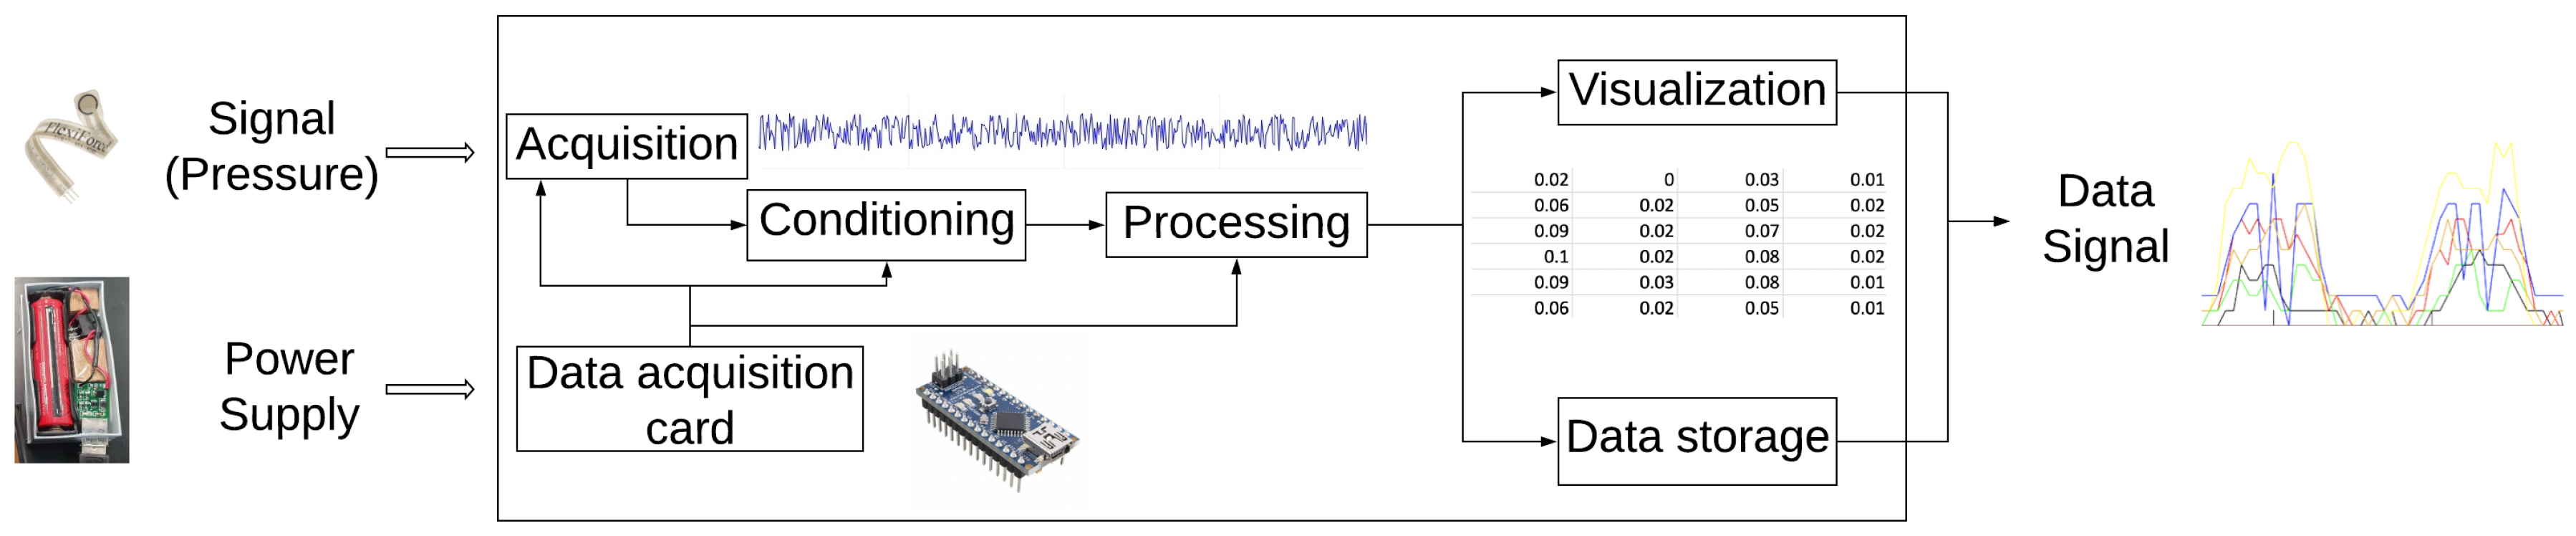

2.1. Materials and Equipment

Pressure System Characterization and Linearization

3.1. Static Characterization

3.2. Comparison Results between F-Socket System and Socket Interface Pressure Device

3.3. SIFP System Test